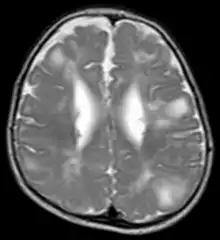

Classic intracranial manifestations of TSC include subependymal nodules and cortical/subcortical tubers.[5]

The tubers are typically triangular in configuration, with the apex pointed towards the ventricles, and are thought to represent foci of abnormal neuronal migration. The T2 signal abnormalities may subside in adulthood, but will still be visible on histopathological analysis. On magnetic resonance imaging (MRI), TSC patients can exhibit other signs consistent with abnormal neuron migration such as radial white matter tracts hyperintense on T2WI and heterotopic grey matter.

Subependymal nodules are composed of abnormal, swollen glial cells and bizarre multinucleated cells which are indeterminate for glial or neuronal origin. Interposed neural tissue is not present. These nodules have a tendency to calcify as the patient ages. A nodule that markedly enhances and enlarges over time should be considered suspicious for transformation into a subependymal giant cell astrocytoma, which typically develops in the region of the foramen of Monro, in which case it is at risk of developing an obstructive hydrocephalus.[6]

A variable degree of ventricular enlargement is seen, either obstructive (e.g. by a subependymal nodule in the region of the foramen of Monro) or idiopathic in nature.